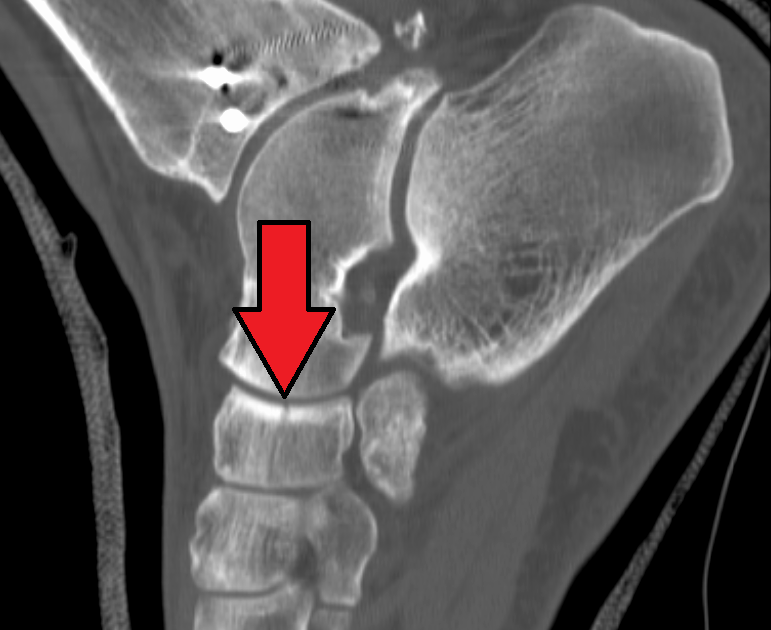

Tarsal Navicular Bone Fracture

Dorsal avulsion fracture of the navicular bone Image Navicular Fracture Cast a nondisplaced fracture in the waist or distal pole of your scaphoid that’s treated soon after injury can be treated by immobilizing your wrist with a cast for six to 12 weeks. The importance of following a strict. your scaphoid is one of your carpal bones, the collection of bones that makes up your wrist. Identify the common. Navicular Fracture Cast.